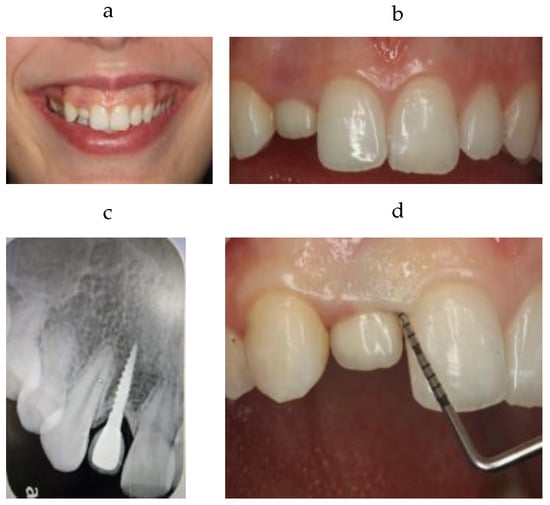

2. Clinical Case

3. Treatment Plan

4. Treatment Sequence